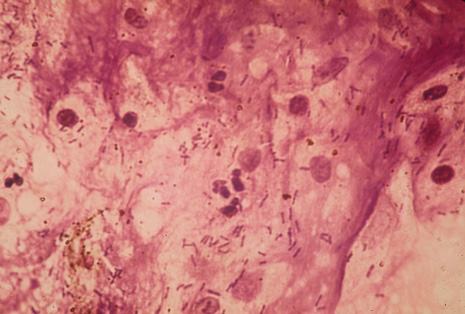

Many forms of uveitis are characterized by specific types of inflammatory cells. Usually, however, one encounters mixtures of cell types in any given specimen, with the relative percentages of lymphocytes and polymorphonuclear leukocytes varying. There may be unusual numbers of eosinophils, or macrophages laden with lens material may be present. Thus, an enumeration of the cells and a careful analysis of their structure can be useful as a diagnostic aid (Figs. 7, 8, 9, 10, 11, 12, 13, 14, 15, 16, 17, 18, 19, and 20). Figure 15 demonstrates eosinophils that were aspirated from the anterior chamber of a patient with Toxocara canis endophthalmitis. Figure 12 demonstrates malignant cell infiltrate from the vitreous, showing the stained presence of monoclonal light chains being elaborated in the cytoplasm. Interleukin-10, detectable in the vitreous of intraocular lymphoma patients, is also directly indicative of both the clinical activity and the number of malignant cells as observed by cytopathology.

Precise identification and culture of bacterial and fungal pathogens from both the aqueous humor and the vitreous fluid can be obtained. Gram's stain and Giemsa's stain smears of centrifuged specimens from the aqueous humor and the vitreous humor frequently demonstrate the bacterial or fungal causative agent. Attempts to isolate bacteria and fungi and to identify them on Gram's stain or Giemsa's stain smears have been most rewarding in the following cases: (a) postoperative endophthalmitis, (b) infection after a penetrating injury of the eye, (c) drug abuse patients with endogenous endophthalmitis (Figs. 21, 22, 23, 24, and 25), (d) patients receiving hyperalimentation, and (4) patients who are immunocompromised as a result of exogenous immunosuppressive agents.